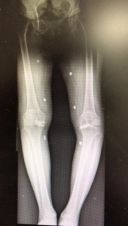

这次也是经人介绍来普陀区中心医院骨科周军杰大夫的专家门诊,原本想配点药吃吃,减轻点疼痛就算了。可是周军杰主任医师一看情况就发现不妙,双侧的膝盖都已经内翻畸形,关节伸屈活动度只有正常的一半都不到,就果断给拍了X光片,一拍片子就知道原来两侧的膝盖都已经到了骨关节炎终末期,严重内翻畸形,看来只能手术,否则情况只会越来越糟糕。

图1 膝关节X光片(可滑动)